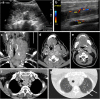

Focal and diffuse thyroid abnormalities are commonly encountered during the interpretation of computed tomography (CT) exams performed for various clinical purposes. These findings can often lead to a diagnostic dilemma, as the CT reflects the nonspecific appearances. Ultrasound (US) examination has a superior spatial resolution and is considered the modality of choice for thyroid evaluation. Nevertheless, CT detects incidental thyroid nodules (ITNs) and plays an important role in the evaluation of thyroid cancer. In this pictorial review, we cover a wide spectrum of common and uncommon, incidental and non-incidental thyroid findings from CT scans. We also discuss the most common incidental thyroid findings, best practices for their evaluation, and recommendations for their management. In addition, we explore the role of imaging in the assessment of thyroid carcinoma (before and after treatment) and preoperative thyroid goiter, as well as localization of ectopic and congenital thyroid tissue.

Teaching points: • Thyroid disorders tend to have non-specific CT appearances. • ITNs are common on neck CT. • ITN management depends on nodule size, age, health status, lymphadenopathy, and invasion. • CT is used in assessment of cancer extension, mass effect, invasion, and recurrence. • CT plays a role in preoperative planning in patients with symptomatic goiter.